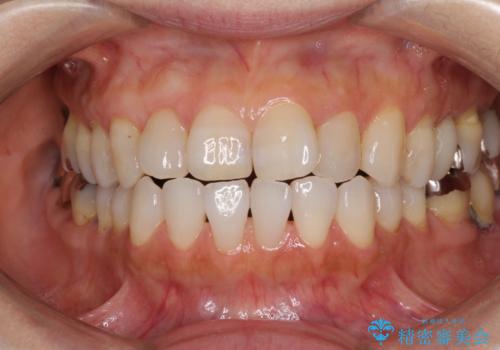

[ 前歯開咬 ] 前歯が噛んでいない マウスピース矯正治療

担当医 大元洋佑

![[ 前歯開咬 ] 前歯が噛んでいない マウスピース矯正治療の症例 治療前](https://seimitsushinbi.jp/wp/wp-content/uploads/2022/11/IMG_4669-500x350.jpg?v=1668218426)

![[ 前歯開咬 ] 前歯が噛んでいない マウスピース矯正治療の症例 治療後](https://seimitsushinbi.jp/wp/wp-content/uploads/2022/11/IMG_2488-500x350.jpg?v=1668218373)